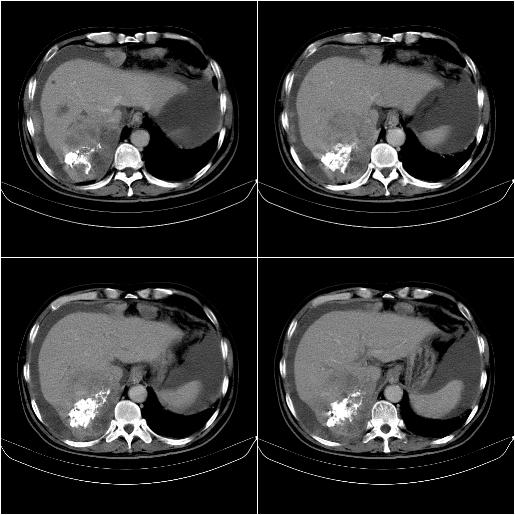

m,67y,肝癌9月,介入术后3月。现腹胀、纳差、腹泻。

1)肝癌介入治疗术后碘油沉积不良。2)门静脉瘤栓形成,腹膜广泛性转移。3)肝硬化,脾大,腹水。4)慢性胆囊炎。